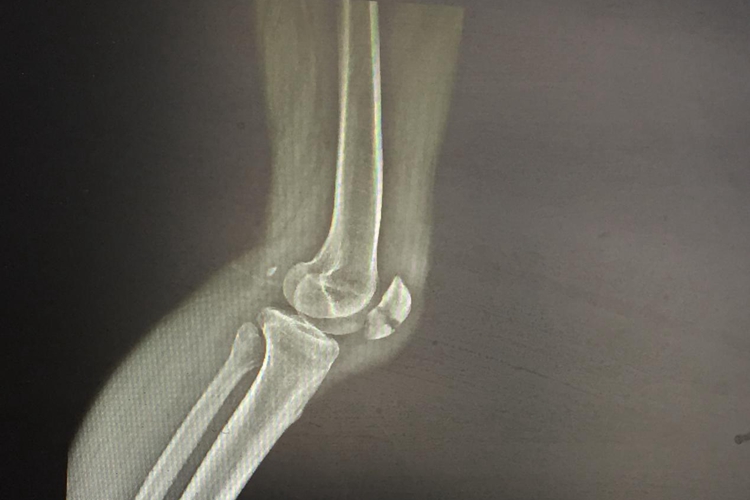

髌骨骨折

髌骨骨折多发生于青壮年。受伤后,膝前方肿胀,有淤斑膝关节不能活动检查可发现髌骨前方有压痛感,受伤早期可扪到骨折分离出现的凹陷,挤压髌骨使疼痛加重。由于关节内积血,可以出现浮髌试验阳性。

髌骨骨折,通常为间接暴力所致,如行走失足滑倒时,膝关节突然屈曲,股四头肌强烈收缩引起髌骨骨折,这类骨折多为横断型骨折,移位较大,直接暴力如撞击、踢伤等引起的髌骨骨折,通常为粉碎性骨折。

髌骨骨折的治疗分为非手术治疗和手术治疗。非手术治疗对于无移位的骨折,可用注射器抽干净关节内积血,下肢后侧用长木板或石膏托固定膝关节伸直位;对于移位横形骨折可先抽出关节内积血,手法复位后,以抱膝圈固定于伸膝位。手术治疗可采用切开复位内固定、髌骨部分切除术、髌骨全切术等。